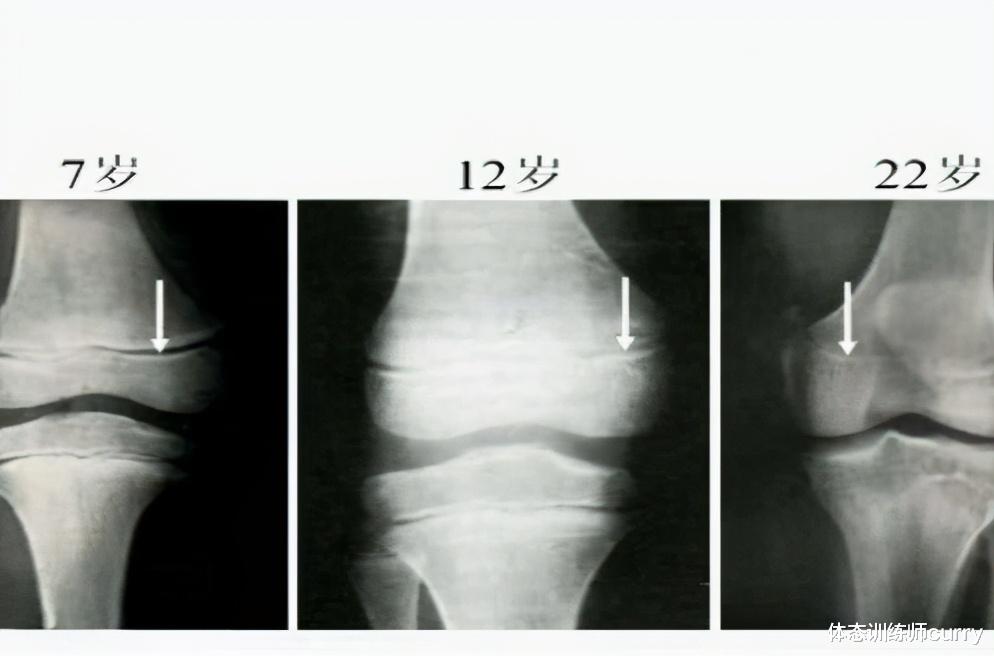

其实这也是一直以来的问题 , 青少年过早的进行力量训练 , 到底会不会影响身体的正常发育 , 针对这一问题 , Paul从骨骼成长方式角度 , 做具体分析:

骨骼生长方式

骨骼的生长方式有两种 , 一种是膜内成骨 , 另一种是软骨内成骨 。

软骨内成骨

是指身体中软骨逐渐被更坚硬的骨骼取代 , 最终形成骨骼 , 身体中的大部分的骨骼都是通过这种形式生成的 。

骨骼生成过程

在我们小的时候 , 还是在妈妈肚子里当胎儿时 , 我们大部分的骨骼都还是软骨 , 随着胎儿生长有了自主意识的活动 , 这时那些软骨的两侧会慢慢长出骨外膜 , 逐渐包裹着软骨 , 而通过成骨细胞带来的各种营养素 , 如蛋白质 , 钙和磷等等 , 在骨骼最外边形成了一圈密质骨 。